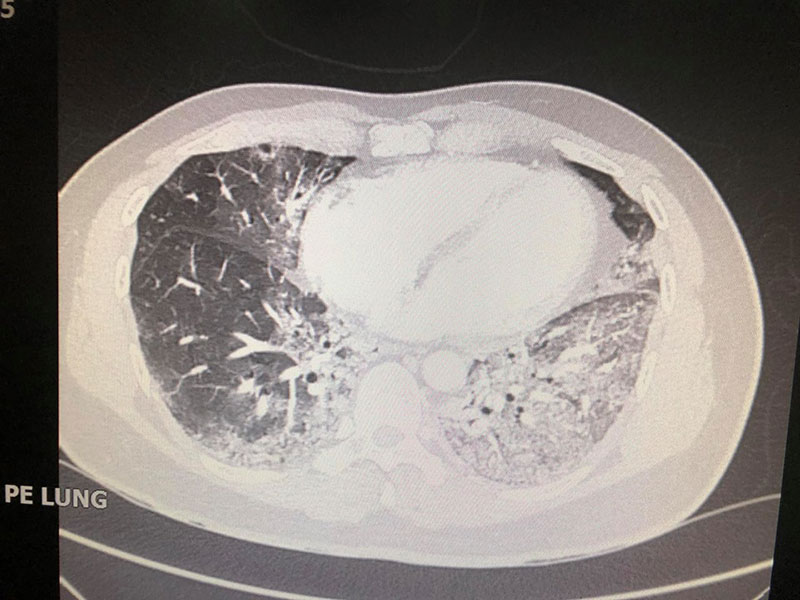

ต่อมา ชายคนดังกล่าวอาการดีขึ้นเล็กน้อย ปอดรั่วดีขึ้น แต่อาการมาแย่อีกทีในวันที่ 17 ที่นอนในโรงพยาบาล ปอดดูแย่ ต้องใส่เครื่องช่วยหายใจ และแม้จะให้ออกซิเจน 100% แล้ว ระดับออกซิเจนในเลือดยังต่ำมาก หมอจึงส่องกล้องเพื่อดูหลอดลม และเห็นตุ่มเล็ก ๆ ในหลอดลมใหญ่ด้านขวา จึงมีการดูดเสมหะและตัดชิ้นเนื้อส่งตรวจ จึงพบเชื้อราเป็นจำนวนมาก